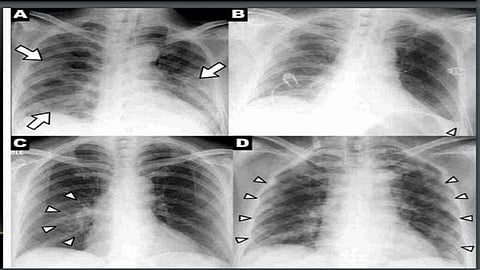

ईएसडीएसमार्फत काही दिवसांपूर्वीच एक्स-रेच्या सहाय्याने कोरोनाचे निदान करण्याचे तंत्र अवगत करण्यात आले आहे. आर्टिफिशियल इंटेलिजन्स (एआय) आणि मशीन लर्निंग या तंत्रज्ञानाचा वापराद्वारे हे शक्य झाले आहे. "ए ए प्लस कोविड-19 टेस्टिंग सोल्यूशन' असे या महत्त्वकांक्षी प्रकल्पाचे नाव आहे. यामध्ये संशयीतांच्या छातीचा एक्स-रे काढून तो ईएसडीएसच्या पोर्टलवर लॉगइन करून अपलोड केल्यानंतर दोन मिनीटांमध्ये कोरोनासंदर्भात निदान होत असल्याचा दावा ईएसडीएसने केला आहे.

या व्हॅनमध्ये एक्स-रे काढण्याची प्रणाली उपलब्ध आहे. ज्या व्यक्तीचा एक्स-रे काढायचा आहे, त्याच्या गळ्यात लॉकेट किंवा अन्य धातूच्या वस्तू असायला नको. व्हॅनजवळ संबंधित व्यक्तीला कॅसेट धरून उभे केले जाते. यानंतर व्हॅनमधील तंत्रज्ञ लांबून या एक्स-रे काढतो. यानंतर कॅसेट सॅनिटाईज केली जाते. काढलेला एक्स-रे पोर्टलवर अपलोड करून कोरोनाबाबतचे निदान करता येऊ शकते.